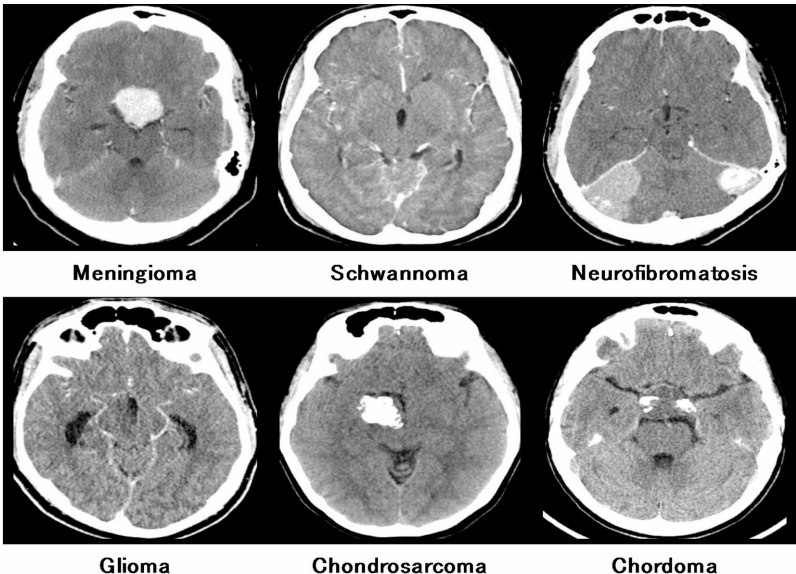

研究团队创新性地整合了自动化预处理、ABTFCS分割和统计多特征优化三大技术模块。采用来自Radiopaedia的900张512×512像素CT图像(含6类肿瘤各150例),通过中值滤波和高斯滤波降噪后,运用不规则多边形种子点划分四个感兴趣区域(ROI)。特征提取阶段融合灰度共生矩阵(GLCM)、直方图和频谱特征,最终通过相关性分析筛选出12个最优特征。分类阶段对比了五种机器学习算法,其中经超参数调优的多层感知器(MLP)表现最优。

MLP在六类肿瘤分类中展现出梯度性能:软骨肉瘤(94.66%)、脊索瘤(98.33%)、胶质瘤(99.16%)、脑膜瘤(98.00%)、神经纤维瘤病(98.83%)和神经鞘瘤(98.00%)。对比实验显示,优化特征使MLP建模时间从34.9秒降至0.8秒,准确率提升至97.83%。